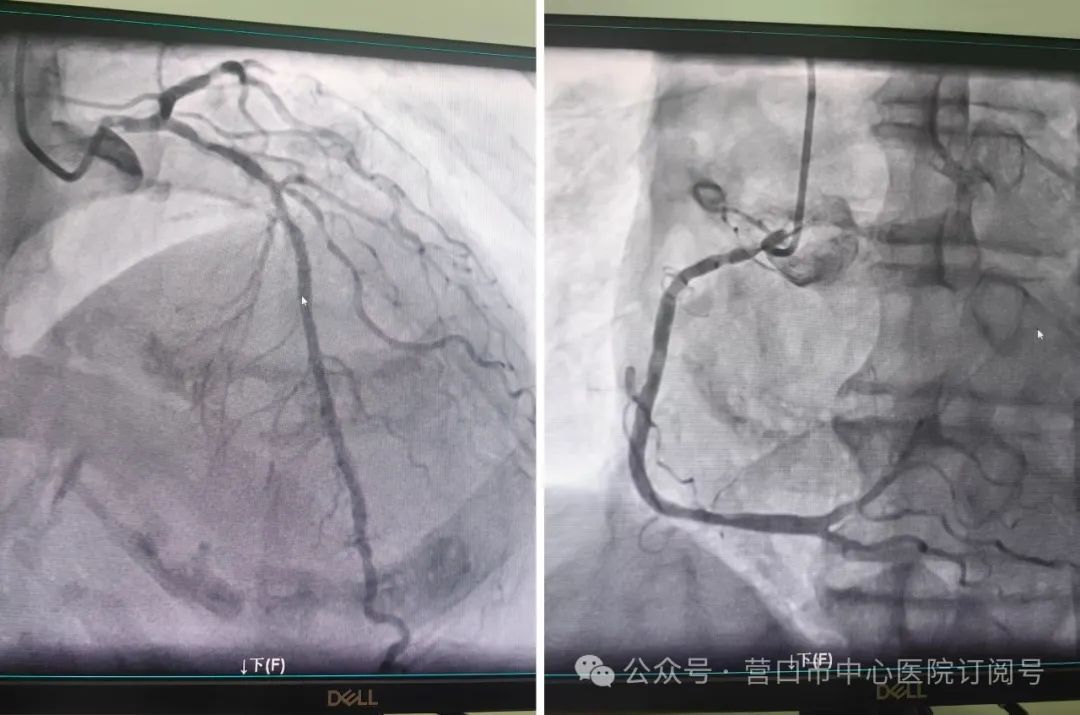

尽管手术指征明确,但患者刚经历直肠癌手术、肾功能代偿能力脆弱,冠脉介入治疗风险极高。经与家属充分沟通并获得全力支持后,2月10日,由曹兴阳、赵振梅医生组成的手术团队迎难而上。

术中发现患者冠状动脉严重狭窄,主刀医生曹兴阳凭借丰富经验,迅速完成动脉穿刺、球囊扩张及支架精准植入,全程仅用30分钟。术后患者胸痛症状即刻缓解,次日复查显示各项指标稳定,无需原计划的透析治疗。